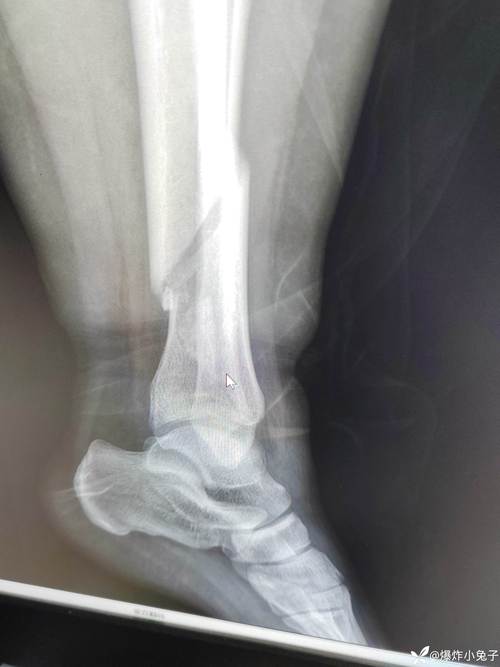

(图片来源网络,侵删)- 骨折或骨裂: 即使是轻微的外伤也可能导致。

- 优点: 价格便宜、普及度高、辐射剂量相对较低,可以很好地观察骨骼的整体形态、关节间隙、骨质增生和明显的侵蚀。

- 缺点: 对于早期的软组织(如滑膜)病变和微小的骨侵蚀不敏感,在风湿病的极早期,X光片可能完全正常。

- 用途: 作为初步筛查和常规随访的必备检查。